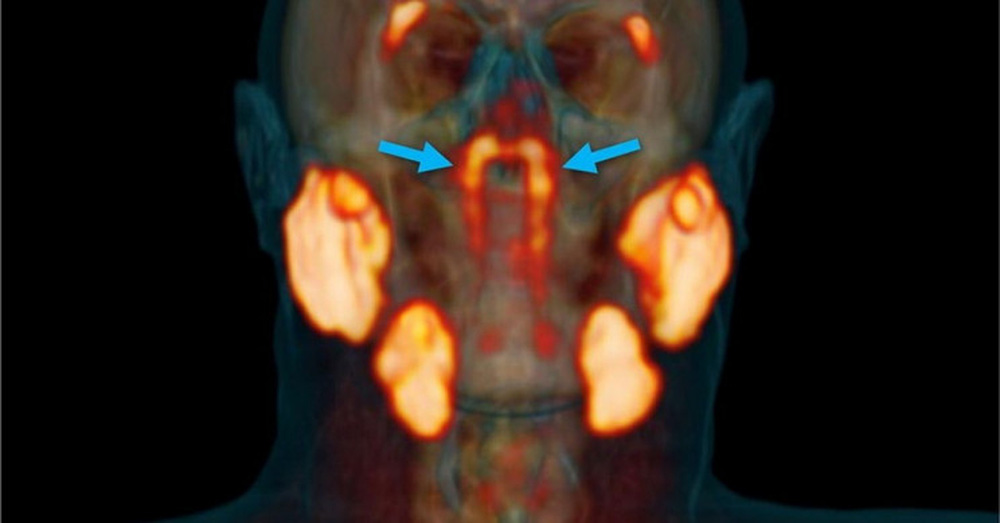

Vào tháng 10/2020, các nhà nghiên cứu đã phát hiện ra rằng con người có một bộ tuyến nước bọt phụ chưa được phát hiện trước đây ngay bên trong đầu của chúng ta.

Hình ảnh trong phát hiện tuyến nước bọt mới vào năm 2020.

Trong phát hiện năm 2020, "thực thể không xác định" đã được phát hiện một cách tình cờ. Một nhóm các nhà khoa học đã nghiên cứu bệnh nhân ung thư tuyến tiền liệt. Họ sử dụng một loại phương pháp chụp hình ảnh tiên tiến gọi là PSMA PET / CT. Và lần này, hình ảnh đã hiện lên một thứ gì đó khác.

Nhà nghiên cứu Wouter Vogel tại Viện Ung thư Hà Lan, giải thích: "Theo những gì chúng ta biết, các tuyến nước bọt hoặc tuyến nhầy duy nhất trong vòm họng có kích thước siêu nhỏ và có tới 1.000 tuyến rải đều khắp niêm mạc. Vì vậy, hãy tưởng tượng sự ngạc nhiên của chúng tôi khi tìm thấy tuyến này."

Trong khi đó, hệ thống tuyến nước bọt được phát hiện bởi nhóm của Tiến sĩ Vogel lớn hơn nhiều, nó nằm sau mũi, phía trên vòm miệng và gần tâm đầu của chúng ta.